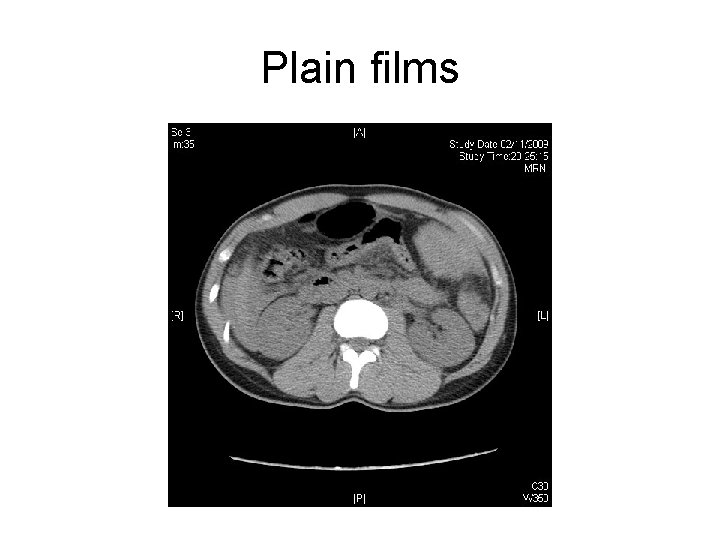

Case 4 • M/24 • He complained of epigastric and LUQ abdominal pain after having been assaulted by someone on two days ago. • PE: tenderness over his LUQ abdomen. No external wound was found. • BP 148/74 mm. Hg P 93/min Sa. O 2 99%

• His BP drop to 60/30 mm. Hg after admission and return to 130/70 mm. Hg after 1000 ml gelofusin infusion. • Urgent CT was performed

Plain films

Questions • 1) describe the CT findings • 2) what is the diagnosis? • 3) What is the abnormal CT findings that indicate surgical intervention ? • 4) what is the management?

Answers • Hyperdense peri-splenic hematoma • Scatter intrasplenic hypodense area, suggestive of hematoma and ischemic area • Curvilinear ill-defined hyperdensities are seen within the hypodense region, suggestive of active bleeding • Contrast brush in intrasplenic hypodense area in delay contrast films

• Dx : intrabdominal hematoma due to splenic laceration and presence of active bleeding • Rx : spleenectomy